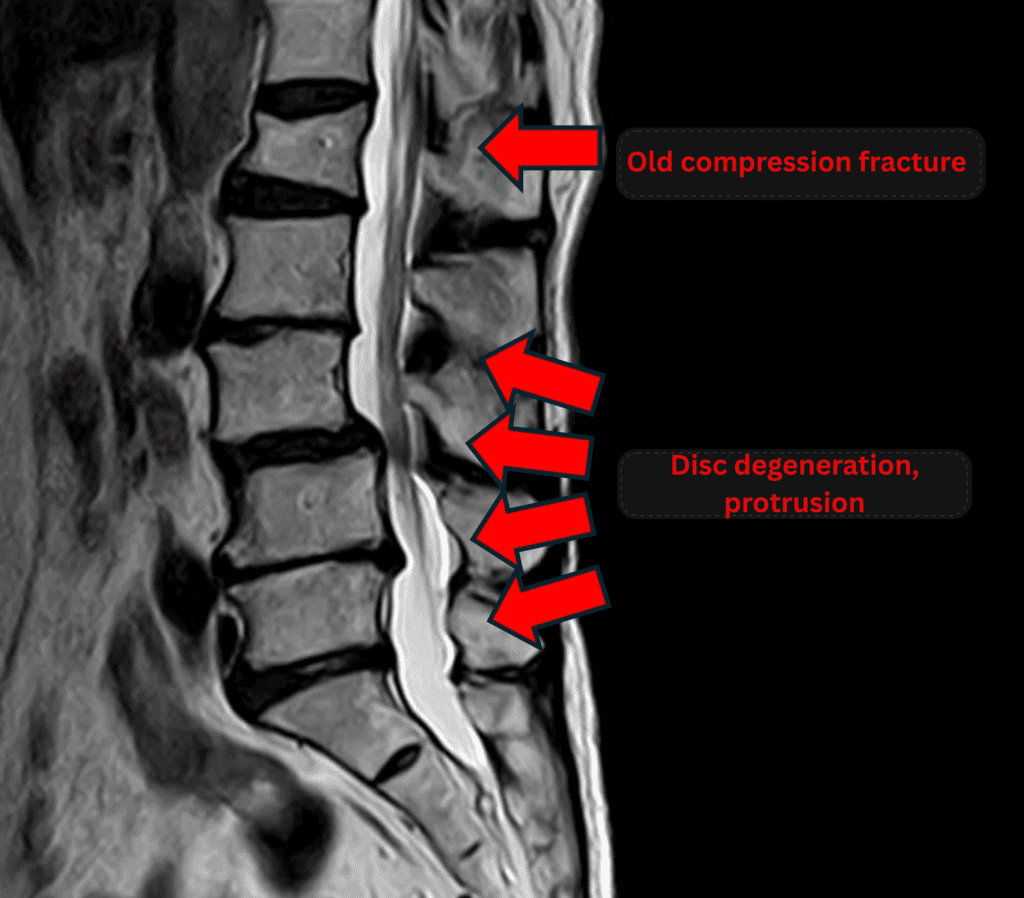

Imaging and findings

- L1: Old (healed) compression fracture

- L2/3: Disc degeneration, bulging, foraminal stenosis

- L3/4: Disc degeneration, bulging, foraminal stenosis, anterior spondylolisthesis

- L4/5, L5/S1: Disc degeneration, bulging, foraminal stenosis, endplate degeneration

The above findings were also observed on the imaging.

Compression of the spinal canal due to disc pathology at L2/3, L3/4, L4/5, and L5/S1 is highly likely the cause of symptoms.